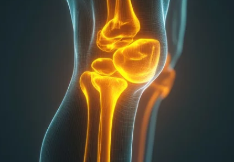

3. 오금 통증을 유발하는 대표적인 질환

① 베이커 낭종(Baker’s Cyst)

✔ 무릎 뒤쪽에 물이 차면서 혹처럼 부풀어 오름

✔ 초기에는 무증상이지만, 커지면 통증 & 붓기 유발

② 반월상연골판 손상(Meniscus Tear)

✔ 무릎 연골이 찢어지거나 마모되면서 오금 부위까지 압박을 느낌

✔ 운동 중 회전 동작에서 손상될 가능성이 높음

③ 좌골신경통(Sciatica)

✔ 허리 디스크나 척추 문제로 인해 좌골신경이 눌려 오금까지 통증 유발

✔ 엉덩이, 허벅지, 종아리까지 저릿한 느낌이 동반될 수 있음

④ 혈전(심부정맥 혈전증, DVT)

✔ 혈액 응고로 인해 다리 혈관이 막히면서 부종 & 통증 발생

✔ 즉시 치료하지 않으면 폐색전증으로 진행될 수 있음(응급 상황)

📌 즉, 오금 통증의 원인은 베이커 낭종, 연골 손상, 신경 문제, 혈관 질환 등으로 다양할 수 있다.